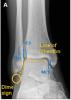

4. Имел ли место у пациента А. «консолидированный перелом наружной лодыжки справа»?